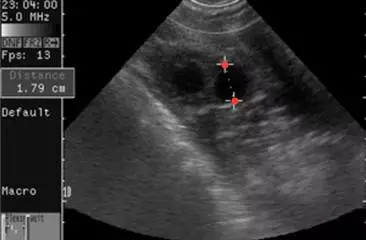

①卵泡呈圆形或椭圆形,直径达15-30mm(21.2+-0.53mm),卵泡内呈无回声区,清亮纯净,边界清晰,壁菲薄。

①卵丘出现率约20%,大多出现在>18mm成熟卵泡中,预测排卵发生在24小时内。